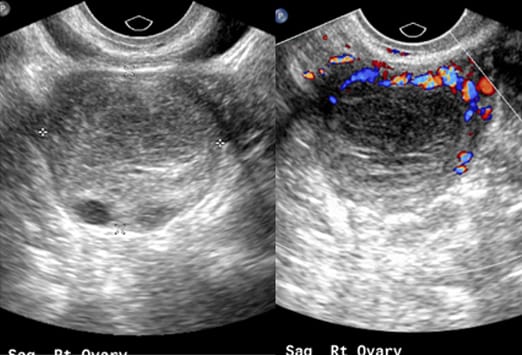

Diese 28-jährige Frau wurde mit seit 7 Tagen bestehenden, rechtsseitigen Unterbauchschmerzen vorstellig. Die zuvor für 15 Jahre durchgeführte Empfängnisverhütung hatte die Patienten vor einigen Monaten abgesetzt. In den letzten Monaten hatte sie rezidivierende Schmerzen im Bereich des rechten Unterbauchs. Im Bereich des Mittelbauchs kam eine zystische Struktur mit lokaler Akzentuierung zur Darstellung (roter Pfeil). Die Appendix zeigte sich unauffällig (blauer Pfeil).

Bei der zuvor beschriebenen Patientin wurde ein transvaginaler Ultraschall durchgeführt. Im Ultraschall ließ sich eine komplexe zystische Struktur im Bereich des rechten Ovars darstellen (links). Die Farbduplexsonographie ergab eine erhöhte periphere Durchblutung (rechts), vereinbar mit einer hämorrhagischen Corpus luteum Zyste. Es wurde eine erneute Verlaufskontrolle nach zwei Menstruationszyklen empfohlen.